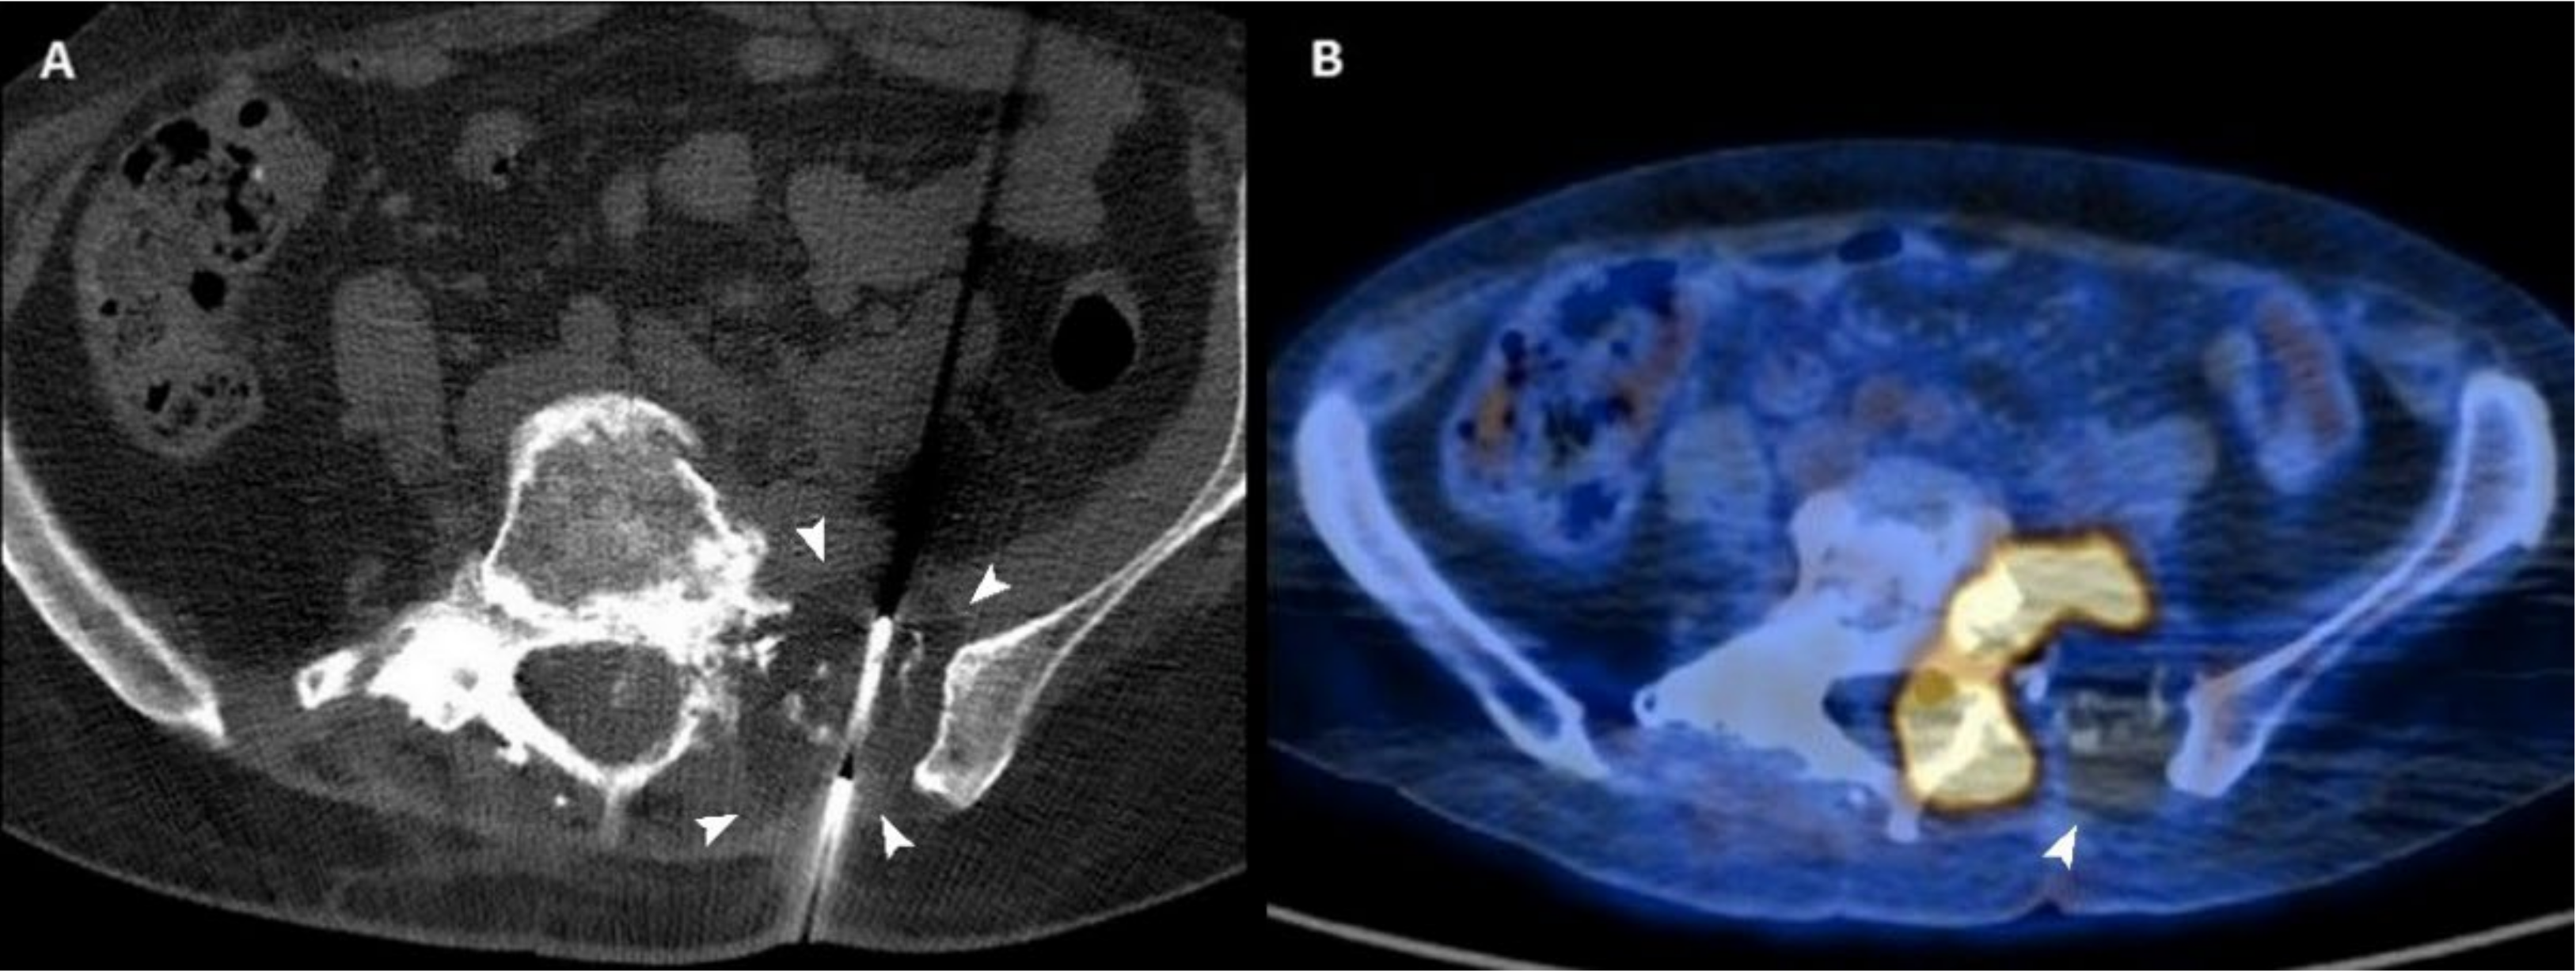

Figure 3.

(A) Axial CT scan of a 54-year-old woman with a sacral metastasis from endometrial sarcoma treated with cryoablation for palliative intent. The ice ball is visible as a hypodense circle surrounding the tip of the needle (arrowheads). (B) 18F-FDG PET/CT scan performed 3 months after the procedure demonstrates the absence of pathologic radiotracer uptake in the ablated area (arrowhead).